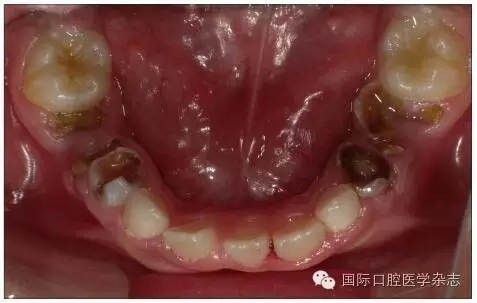

牙齒數(shù)目過多是指多于正常牙類、牙數(shù)以外的額外牙,又稱為多生牙。牙齒數(shù)目過多除多生牙外,還可表現(xiàn)為牙瘤。多生牙可在牙列中多生一顆或幾顆牙,較少見于乳牙列,多見于混合牙列和恒牙列。最常見發(fā)生于上頜前牙區(qū)域。上頜發(fā)生率大約是下頜的8倍。最多見的多生牙是正中牙,位于兩顆上頜中切牙之間。多生牙和牙瘤常導(dǎo)致正常恒牙發(fā)育和萌出障礙,可表現(xiàn)為恒牙遲萌或阻生、牙根彎曲、牙齒移位或萌出方向的改變,伴隨表現(xiàn)有乳牙滯留、鄰牙扭轉(zhuǎn)、牙間隙出現(xiàn)等(如圖5所示)[5]。

個別牙先天缺失常常造成牙列異常間隙,多數(shù)牙先天缺失會影響咀嚼功能和牙列形態(tài),嚴重者影響面容和美觀。牙齒的形態(tài)異常,如融合牙等會使牙弓大小、形態(tài)及咬合關(guān)系發(fā)生異常。乳牙滯留是指繼承恒牙已經(jīng)萌出,未能按時脫落的乳牙。乳牙牙根未吸收或非典型性吸收可導(dǎo)致恒牙萌出方向改變、位置異常,常見于下頜乳中切牙滯留,恒中切牙于舌側(cè)出齦,呈現(xiàn)“雙排牙”現(xiàn)象(圖5)。上頜牙齒在滯留乳牙腭側(cè)出齦則可能形成反(圖6)。

640.webp (4).jpg

左:口內(nèi)照;右:X線片。

圖5 上頜前牙區(qū)多生牙導(dǎo)致上頜中切牙間隙,右上中切牙扭轉(zhuǎn)

Fig 5 Supernumerary teethin the area of maxillary anterior teeth caused incisor gap, reversed rightupper incisor

640.webp (5).jpg

圖6 右上乳中切牙遲脫引起右上中切牙腭向異位萌出

Fig 6 Late exfoliation ofright upper primary incisor caused ectopicpalatal eruption of right upper incisor